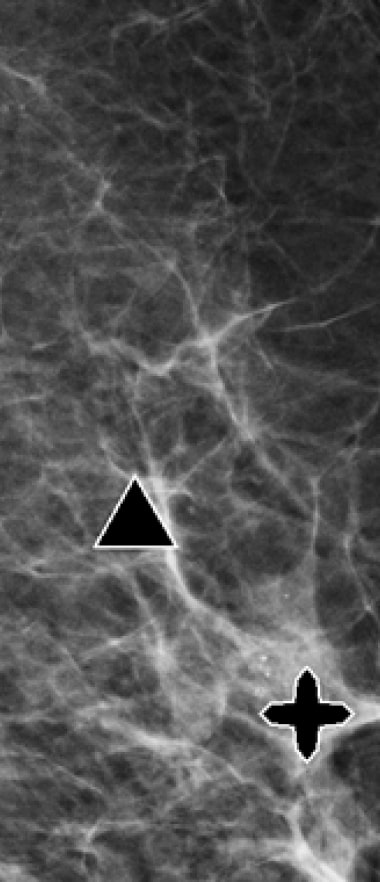

ImageChecker® 2D CAD analyzes conventional 2D mammography images to help detect potential breast cancer. When it comes to effectiveness, this system has shown an increased detection rate of breast cancer, and it’s particularly effective in women with dense breast tissue. The system is compatible with a variety of workstations and Hologic mammography machines, enabling a more timely diagnosis.

Hologic R2 CAD is one of the best mammography imaging systems available on the market. It uses advanced artificial intelligence or AI-based algorithms to analyze the imaging results, allowing it to recognize lesions and regions of significance in mere seconds. By highlighting potential abnormalities for further inspection by the radiologist, the R2 Cenova allows for much quicker detection and diagnosis.